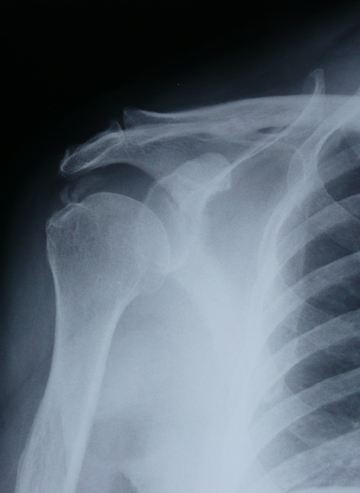

X線画像

肩峰突起と骨頭の間の滑液包の中?に舟状の石灰が

2つ見える。